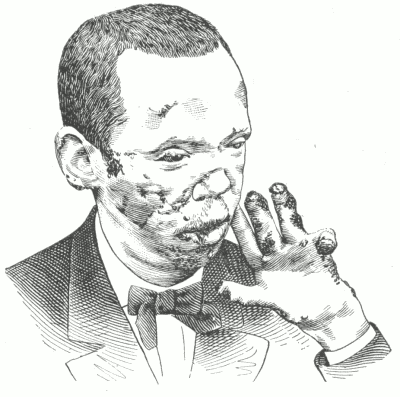

Dermatitis medicamentosa. Bullous dermatitis from iodide of potassium.